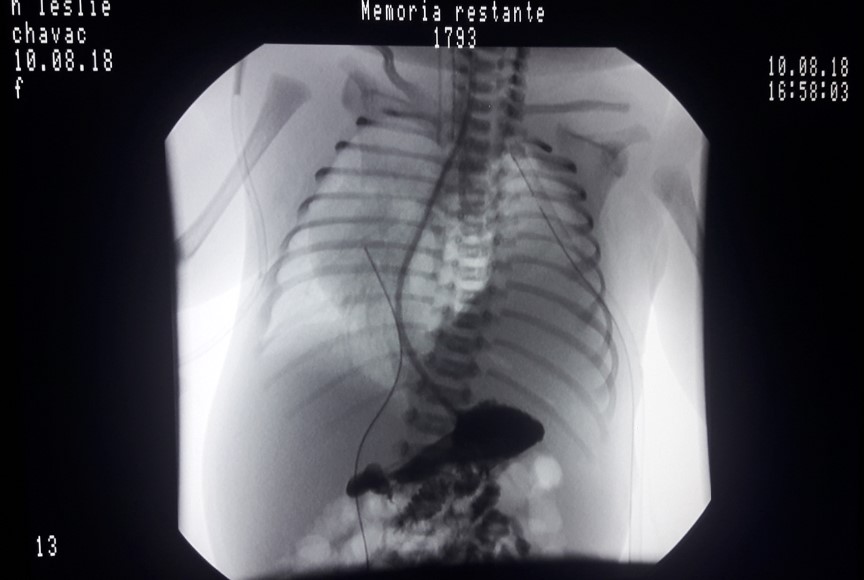

La tomografía axial computarizada (TAC) torácica evidenció una masa sólida de 10 cm x 8 cm x 8 cm en la base del hemitórax izquierdo (Figura 2), lo que resultó en el desplazamiento mediastinal. En el lóbulo superior izquierdo se observó una atelectasia por compresión.

Figura 2. Tomografía axial de tórax.

Se observa una masa solida que ocupa la región basal del hemitórax izquierdo, hay desplazamiento de las estructuras mediastinales hacia el lado contralateral.